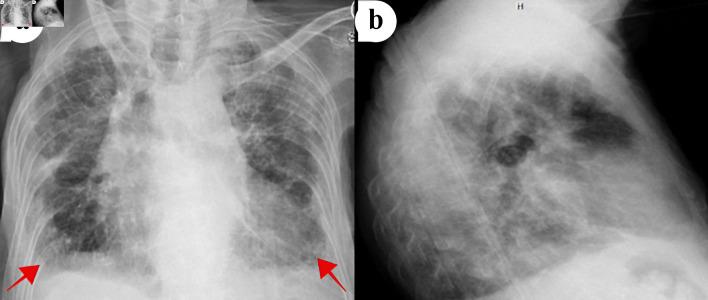

Idiopathic pleuroparenchymal fibroelastosis (IPPFE) is a rare form of idiopathic interstitial pneumonia. The disease is characterized by fibrosis of the pleura and subpleural lung parenchyma predominantly affecting the upper lobes. Various triggers have been proposed as inciting factors in the development of the disease. Diagnosis is made clinically in conjunction with radiographic findings and histopathology when available. There are no known effective treatment options and several cases of lung transplantation have been reported. We report a case of an 86-year-old female who presented to the emergency department with worsening dyspnea and hypoxia. She had a history of unexplained pneumomediastinum and a 20 - 25 pounds unintentional weight loss over 10 months. Computed tomography (CT) of the chest without contrast revealed radiographic evidence of IPPFE. Despite symptomatic management with antibiotics, diuretics, and steroids, her condition continued to deteriorate. Unfortunately, our patient was not a candidate for a lung transplant. She was transitioned to hospice care and succumbed to her disease. IPPFE is a rare disease with an unknown prevalence. It has a median survival rate of 2 years. Usually, there is an overlap with interstitial lung diseases, making it challenging to diagnose. There are only a few cases reported in the literature, and there are currently no guidelines available on the appropriate management of this debilitating disease. We recommend more cases be reported, and further research is done to establish better criteria for diagnosis and management.

特发性胸膜肺实质纤维弹性组织增生症(IPPFE)是一种罕见的特发性间质性肺炎。该疾病的特征是胸膜和胸膜下肺实质纤维化,主要累及上叶。已提出多种触发因素作为该疾病发展的诱发因素。诊断需结合临床、影像学表现以及如有条件时的组织病理学检查来做出。目前尚无已知有效的治疗方案,已有数例肺移植的报道。我们报告一例86岁女性患者,因呼吸困难和低氧血症加重就诊于急诊科。她有不明原因的纵隔气肿病史,且在10个月内体重意外减轻了20 - 25磅。胸部非增强计算机断层扫描(CT)显示有IPPFE的影像学证据。尽管使用抗生素、利尿剂和类固醇进行了对症治疗,但其病情仍持续恶化。不幸的是,我们的患者不符合肺移植条件。她被转至临终关怀护理,最终因病去世。IPPFE是一种罕见疾病,患病率未知。其平均生存率为2年。通常,它与间质性肺疾病存在重叠,这使得诊断具有挑战性。文献中仅报道了少数病例目前尚无关于这种使人衰弱疾病的适当管理的指南。我们建议报告更多病例,并进行进一步研究以建立更好的诊断和管理标准。